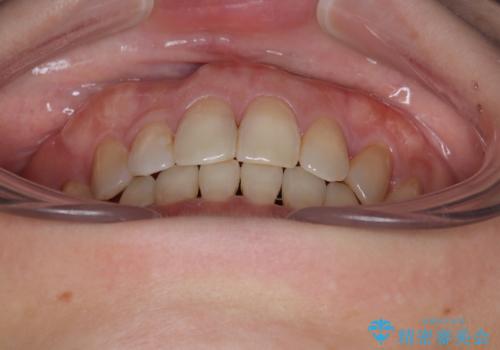

- 前歯のデコボコと口元の突出感を気にして来院された患者様です。

上下前歯がくちばしのように突出していたため、上下左右の第一小臼歯4本を抜歯し、ワイヤー装置にて矯正治療を行うこととしました。

上顎骨に対して下顎骨がやや前方位に位置しているため、歯肉退縮を回避するために下顎前歯をあまり内側に移動させることができない状況でしたが、十分に口元の突出感を改善することができました。